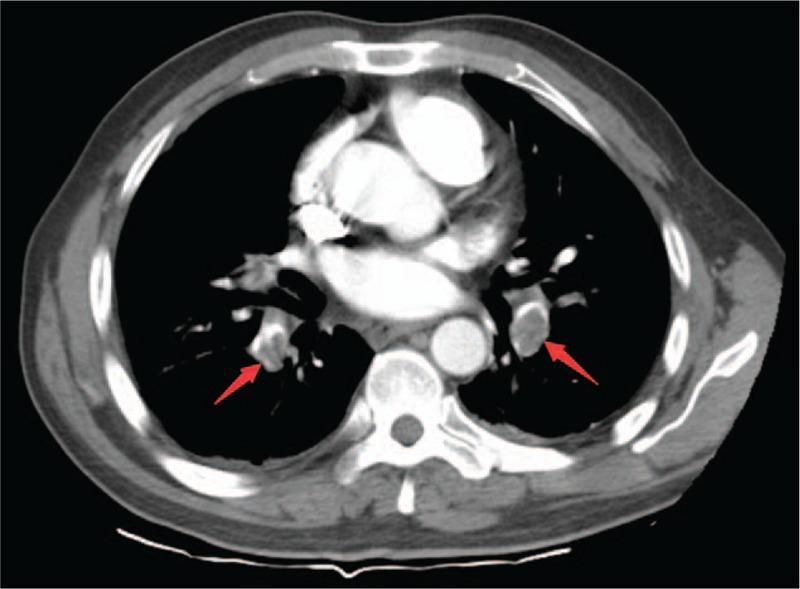

The patient was initially misdiagnosed as cholecystitis and pneumonia, and later was diagnosed as PE by computed tomography pulmonary angiography (CTPA).

https://cdn.ncbi.nlm.nih.gov/pmc/blobs/1ae3/6946195/97a7500b7409/medi-98-e17791-g001.jpg